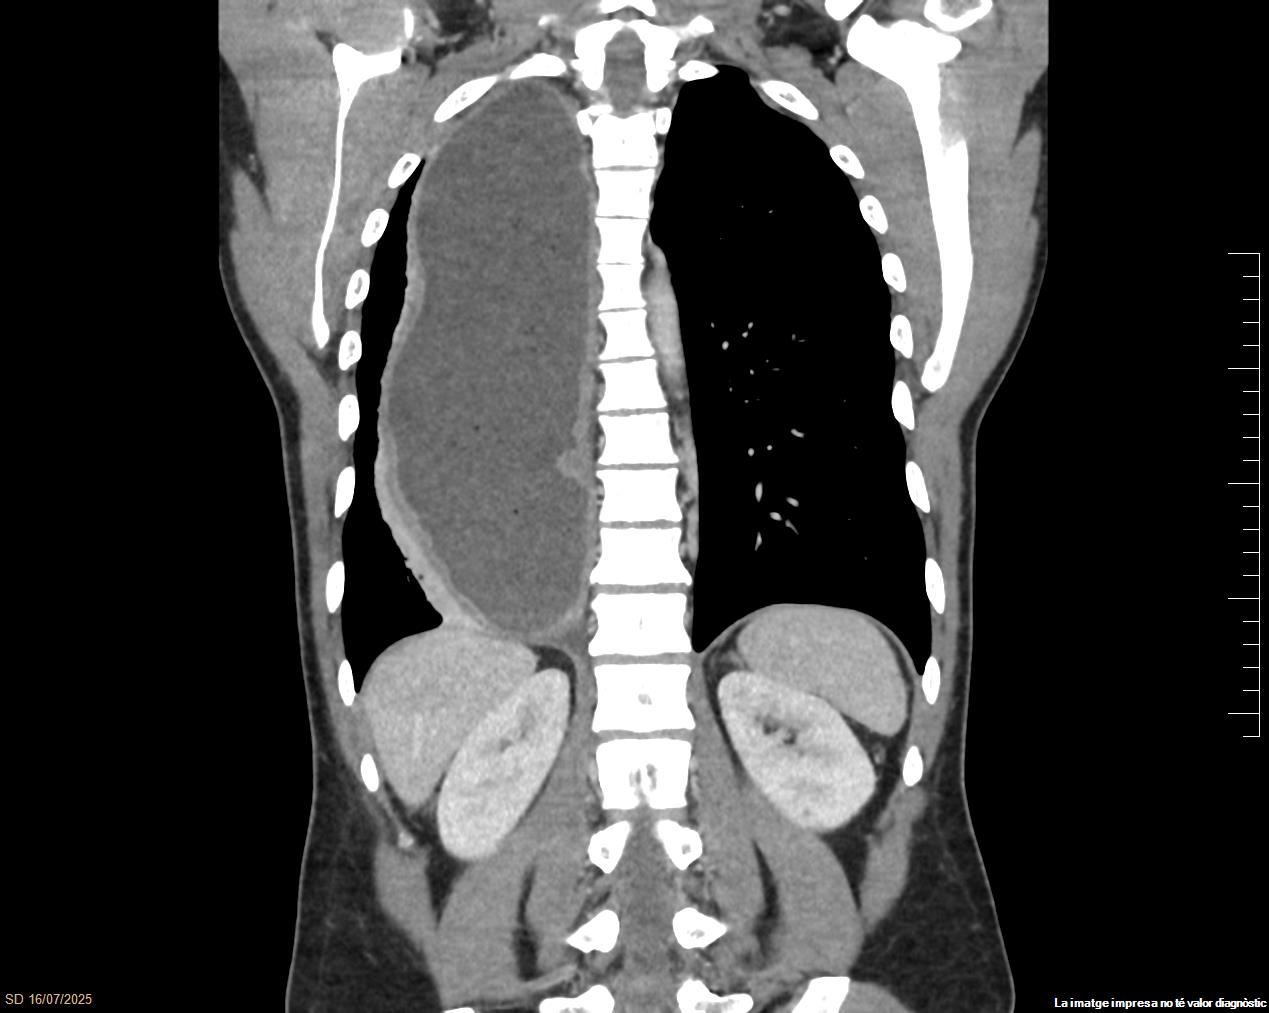

Radiografía simple de tórax (Fig. 1) que informa de gran dilatación de todo el esófago con retención de contenido alimentario, sugiriéndose la realización de un estudio de motilidad esofágica previo a descartar posible proceso neoformativo distal. Por este motivo y junto a la presencia de síndrome tóxico se solicita TC torácico con contraste (Fig. 2) que describe una importante dilatación esofágica difusa, con importante contenido de retención, adelgazamiento en punta de lápiz de la unión esofagogástrica en plano coronal, y sin claras masas ni tumoraciones, hallazgos compatibles con la posibilidad de una acalasia. También se visualiza una atelectasia laminar de aspecto reactivo a nivel del lóbulo inferior derecho, en relación con la impronta mediastínica secundaria a la dilatación esofágica descrita.